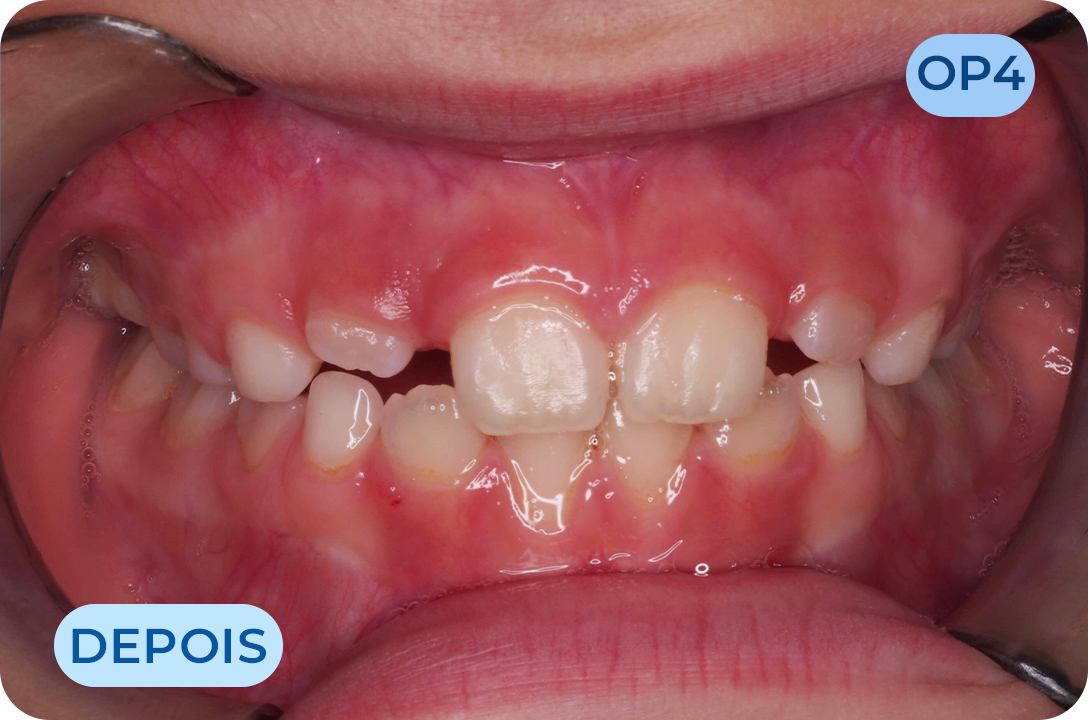

Odontopediatria

Especialidade da Medicina Dentária dedicada à manutenção da saúde oral dos bebés, crianças e adolescentes. Uma dentição definitiva saudável começa na infância com a prevenção e cultivo de hábitos saudáveis. Temos profissionais com formação específica na área, preparados com a tecnologia adequada para facilitar a consulta. Como a saúde do bebé começa antes do nascimento, todas as mães devem ser aconselhadas em relação aos cuidados antes e após o parto, na consulta de odontologia pré-natal que temos disponível na nossa clinica.